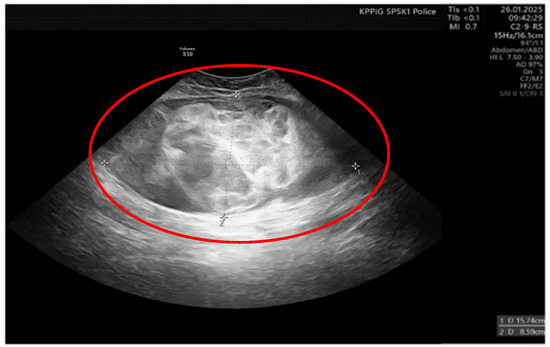

The histopathological blocks from the operation were then re-analyzed in Warsaw. A FISH DDIT3 test and an additional IHC test were ordered. In the assessment of rearrangements within the DDIT3 gene, 95% of the examined cells were confirmed to be neoplastic. Tumors having round cell components higher than 5% of all tumor volumes were considered high grade (9% in this case). The below image (Figure 4) indicates rearrangements within the DDIT3 gene (12q13). In addition, the IHC confirmed SOX 11 (+). The FISH test results confirmed the diagnosis of myxoid liposarcoma. Due to the focally increased cellularity of the lesion, the diagnosis was changed to high-grade MLPS FNCLCC (Federation Nationale de Centros de Lutte Contre le Cancer) Grade 2 (G2) (Figure 4). In a chest CT scan, MRI of both lower limbs, abdominal—pelvic CT, and MRI of the whole body, there were no signs of metastases (M0 N0). The treatment plan changed during the preparation of this article. The first plan was to prepare the patient for a specific expert orthopedic oncology operation; however, after seeing the NGS and FISH results and changing the diagnosis to high-grade myxoid liposarcoma, an oncological committee review (tumor board review) was performed. This tumor board always includes a surgeon specializing in the relevant area, a clinical oncologist, a geneticist, a radiation therapist, and a chemotherapist. The decision was to perform neoadjuvant radiotherapy and chemotherapy before the operation (Figure 3). The patient gave written consent to publish the description of her case.

Figure 4.

Microscopic image from the Department of Soft Tissue/Bone Sarcoma and Melanoma Maria Skłodowska-Curie Memorial Cancer Center in Warsaw. High-grade MLPS FNCLCC (Federation Nationale de Centros de Lutte Contre le Cancer) Grade 2 (G2). (A) H&E (hematoxylin and eosin steins) 20× (B) H&E 40×.